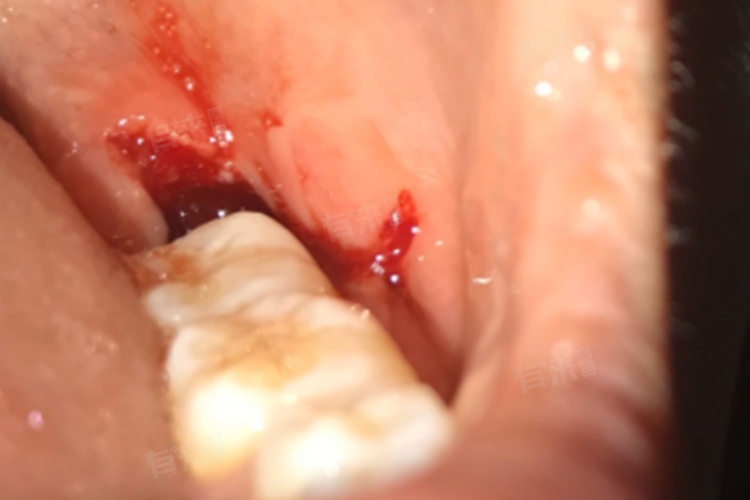

拔牙后第二天的注意事项

- 进食后可以使用清水或医生推荐的漱口水轻轻含漱,将口腔内的食物残渣清理干净,保持口腔清洁,防止细菌滋生,但注意不要触及拔牙创口。不要用舌头舔或吸吮拔牙创口,也不要用手触摸,以免破坏血凝块,增加感染的风险。尽量避免张大嘴巴,防止创口受到外力牵拉。